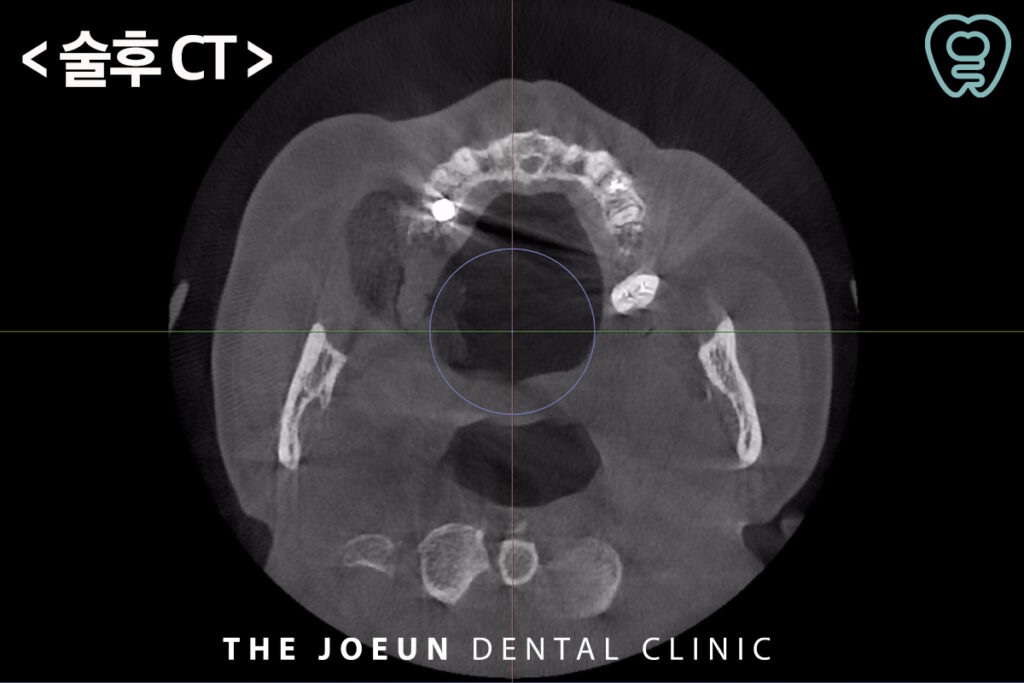

식립 약 4개월 뒤 최종 보철물까지 완료하였습니다.

저희 다사치과 강창더좋은에서는 정밀한 진단을 위하여 3차원적 분석이 가능한 3D CT 장비를 활용하여 구강 구조를 면밀하게 파악하여 치료 계획을 수립하여 꼼꼼하고 섬세한 진행 과정과 치료가 종결되었다고 해서 끝나는 것이 아닌 체계적인 사후관리 시스템까지 갖추어 수준 높은 진료가 가능합니다. 항상 환자분들을 위해 연구하고 노력하겠습니다. 감사합니다!